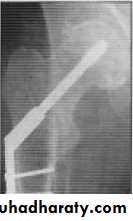

Type 3 & 4: closed reduction + internal fixation if faileda- age <60 years ORIF

b- age >60 years partial hip replacement (Austin moore)

• avascular necrosis treated by partial or total hip replacement.

• Non union treated either by (ORIF + bone graft ) or hip replacement.